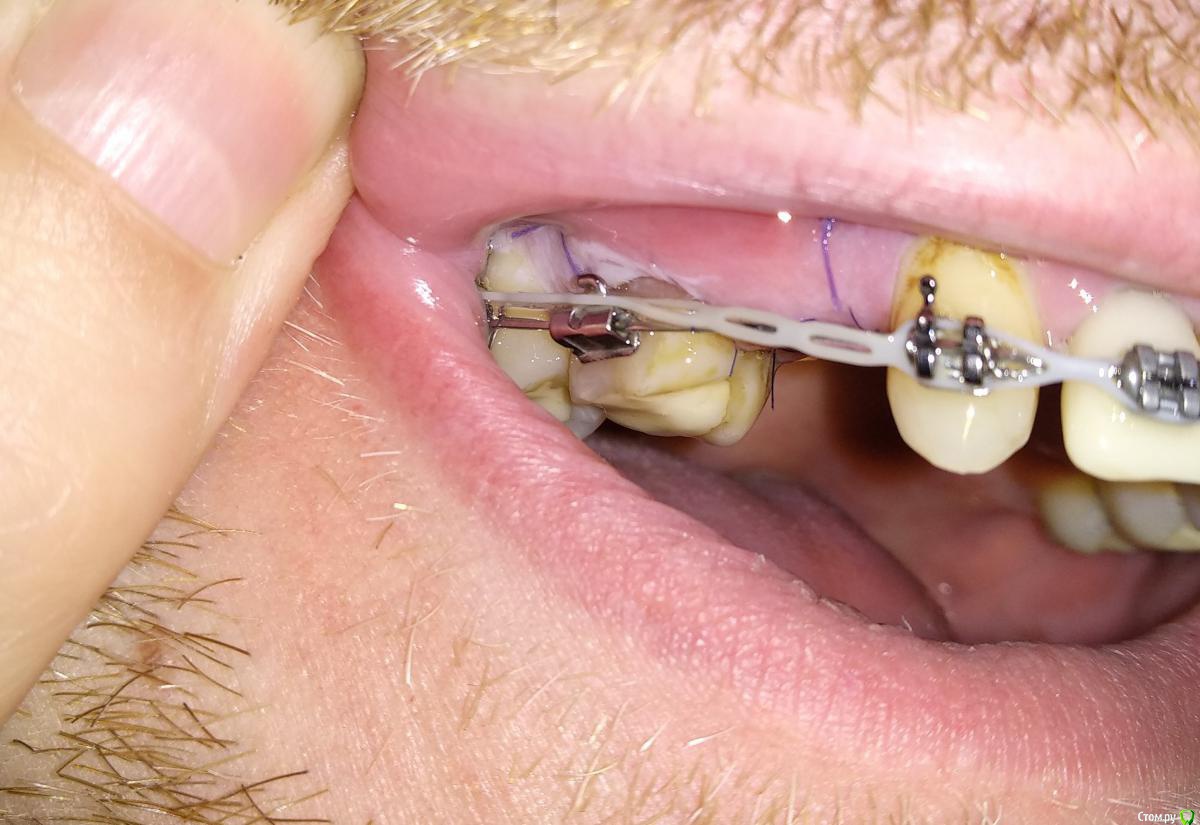

Al..ks Опубликовано 2 июня, 2019 Поделиться Опубликовано 2 июня, 2019 Прошла 30 мая имплантация 14 (3,5*9 Astra + заглушка - торк слабый. Изначально планировался сразу формирователь, но этот вариант мне больше по душе) + подсаживали десну к 16 (снимки КТ чуть позже добавлю). Пил сумамед, немисил (гадость походу - кишки крутило с него), лоратадин - три дня. Сейчас только ванночки хлоргексидина (хотя хирургическая щетка лежит с 12тыс щетинками, но забыл когда ей пользоваться начинать) Была слегка припухлость - на сегодня начала спадать остался только желтый синяк (как его побыстрее свести?)Вопрос по десне я правильно понимаю, что в районе швов это фибриновый налет? А вокруг 16-17 это тоже самое или пора панику наводить? Спасибо за ответы Ссылка на комментарий